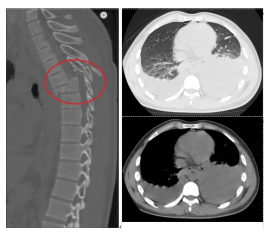

2024年07月17日凌晨1时,骨科值班医师黄孝明接到急诊科紧急会诊请求,患者是一位来自若尔盖县23岁刚大学毕业的待业青年,车祸伤致头胸部疼痛、流血、双下肢截瘫9小时,查体:血压82/68mmHg,胸5以下平面感觉减退,胸6平面以下感觉完全消失,双下肢肌力0级,急诊胸椎CT提示“胸5/6骨折伴脱位”,初步考虑合并胸部脊髓横断伤,需手术治疗。因手术涉及上胸段水平,置钉难度大、术中透视要求高,值班医师当即电话请示吴俊一主任医师并汇报此事,鉴于患者病情,让患方自主选择。患方知晓病情及手术利弊后,经慎重考虑决定在州人民医院诊治和手术。

患者入住骨科后,因损伤重,失血多,血压低,考虑有“失血性贫血、低容量性休克、急性肾功能不全”,当日凌晨予急诊输血治疗,复查血红蛋白仅86.00g/L。颈椎核磁共振(MRI)证实“胸部脊髓横断伤(胸5/6平面)”,患者还合并“左6-8肋骨折、创伤性胸腔积液”,潜在肺损伤、胸腔积液随时加重可能,且存在压疮、肺部感染、深静脉血栓、尿路感染等高风险,病情危重、复杂。患者年轻,尽管脊髓横断伤,预后极差,但主管医师黄孝明主治医师仍尽可能想为患者尽早安排手术,依据病情需要,第一时间请口腔科、耳鼻喉科、胸外科、麻醉科等多学科MDT联合会诊,积极完善术前检查及准备,及时准备胸椎手术耗材,骨科医护团队尽早启动加速康复外科治疗(ERAS),积极防治肺部感染、压疮、深静脉血栓、营养不良、尿路感染、胃肠功能紊乱、便秘等并发症,同时加强患者及家属心理疏导。

在麻醉科、胸外科、输血科、重症医学科等多科室的配合下,患者于2024年07月18日由骨科吴俊一主任医师主刀、宿瑞强主治医师、黄孝明主治医师等配合下,在全麻下进行了“经后路胸6椎体骨折、胸5/6椎脱位切开复位胸3-8钉棒系统(8钉2棒)内固定术+胸5-6椎管扩大减压+硬脊膜修补术+自体骨、人工骨椎板后、关节突植骨融合术”。术前胸外科先行“双侧胸腔闭式引流术”。术后转入重症医学科重症监护治疗。术中使用了关键设备——超声骨刀,为脊柱椎管扩大减压大大节省了时间,止血彻底;术中同时使用了另一神器,可谓“千里眼”的“C臂X光机”,为手术安全性提供了强有力的保障。